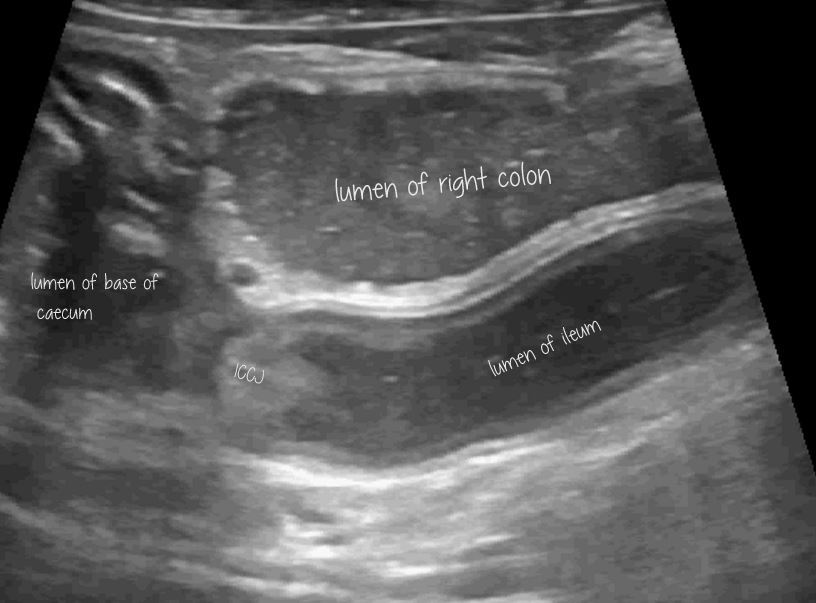

Enteritis after transiting foreign body in a dog

Some things just never make it into textbooks! Or at least it’s difficult to find a specific account of an actual case. This is a 4 y.o. dog who lives in a house where a sock went missing and presented after a few days vomiting. He has no history of illness of prior gastrointestinal signs. … Continue reading